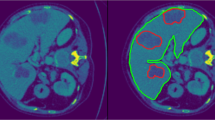

Image segmentation is one of the most popular methods in automated computational medical image analysis. Precise and significant semantic segmentation on abdominal Magnetic Resonance Imaging (MRI) and Computer Tomography (CT) volume images, specifically liver segmentation has a lot of contribution towards clinical decision making for patient treatment. Apart from the many state-of-the-art methods, different cutting-edge deep learning architectures are being developed rapidly. Those architectures are performing better segmentation while at the same time outperforming other state-of- the-art models. Different deep learning models perform differently based on cell types, organ shapes and the type of medical imaging (i.e. CT, MRI). Starting from 2D convolutional networks (CNN), many variations of 3D convolutional neural network architectures have achieved significant results in segmentation tasks on MRI and CT images. In this paper, we review performance of different 2D and 3D CNN models for liver image segmentation. We also analyzed studies that used variants of ResNet, FCN, U-Net, and 3D U-Net along with various evaluation metrics. How these variants of 2D and 3D CNN models enhance the performance against its state-of-the-art architectures are demonstrated in the results section. Besides the architectural development, each year, new segmentation and other biomedical challenges are being offered. These challenges come with their own datasets. Apart from challenges, some datasets are provided and supported by different organizations. Use of such data set can be found in this study. Moreover, this review of reported results, along with different datasets and architectures will help future researchers in liver semantic segmentation tasks. Furthermore, our listing of results will give the insight to analyze the use of different metrics for the same organs with the change in performances.